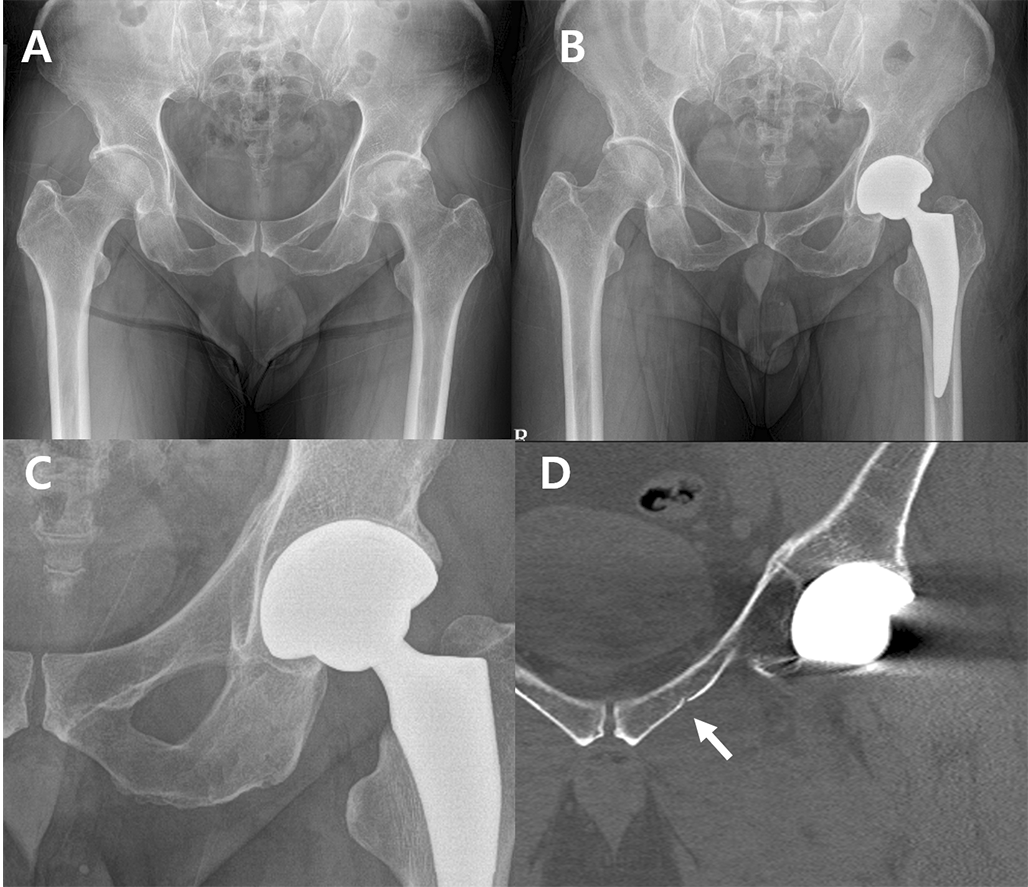

Fig. 2

Radiographs showing superior pubic ramus fracture during total hip arthroplasty. (A) Preoperative anteroposterior view. (B) No fracture lines are visible on the postoperative hip anteroposterior radiograph. (C) Magnified view. (D) The postoperative hip computed tomography coronal view shows incomplete fracture lines (arrow) on the left superior pubic ramus

Occult fractures were most frequently found in the superior pubic ramus, accounting for 10 out of 22 hips (45.4%) (Figs. 2 and 3). Fractures of the inferior pubic ramus were observed in 9 hips (40.9%) (Fig. 4), while 1 hip (4.5%) exhibited fractures in both pubic rami. Fractures involving the peri-acetabulum were observed in 2 hips (9.0%), with one hip showing an extension of the fracture into the superior pubic ramus and the other hip showing extension of the fracture into the inferior pubic ramus. No fractures were observed in the pubic symphyseal area (Table 1).